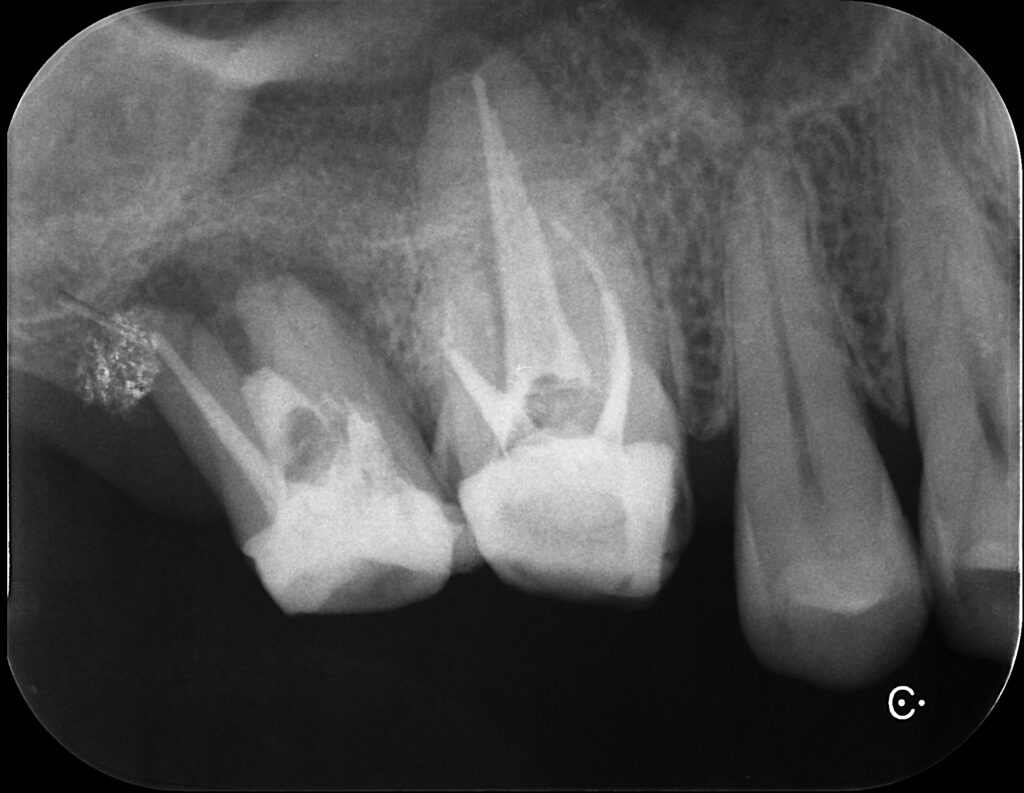

こちらはデンタルX線写真

赤丸の部分。根尖病巣によって黒くなっており、骨が溶けていて炎症が見られます。

揺れているのは一番奥でしたが。

両方根管治療した方が良さそうですね。

7番(一番左)にぶっといコアが‥😅

洗浄している最中の写真

(コア外すの大変だった‥)

右側の写真は6番根管充填後。GP使用。